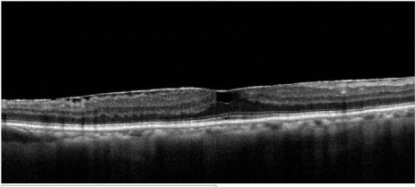

主要藉由眼科醫師在散瞳後,利用 ①眼底鏡直接檢查黃斑部是否有異狀。近年來檢查儀器的進步 ②光學同調斷層儀(OCT),利用先進的光學技術快速掃描後,可以取得清晰的玻璃體視網膜介面及視網膜黃斑部影像。 ③螢光眼底圖FAG也幫助醫生更早一步檢查出肉眼不易察覺的早期病變。

圖2:黃斑部皺摺光學同調斷層儀圖OCT